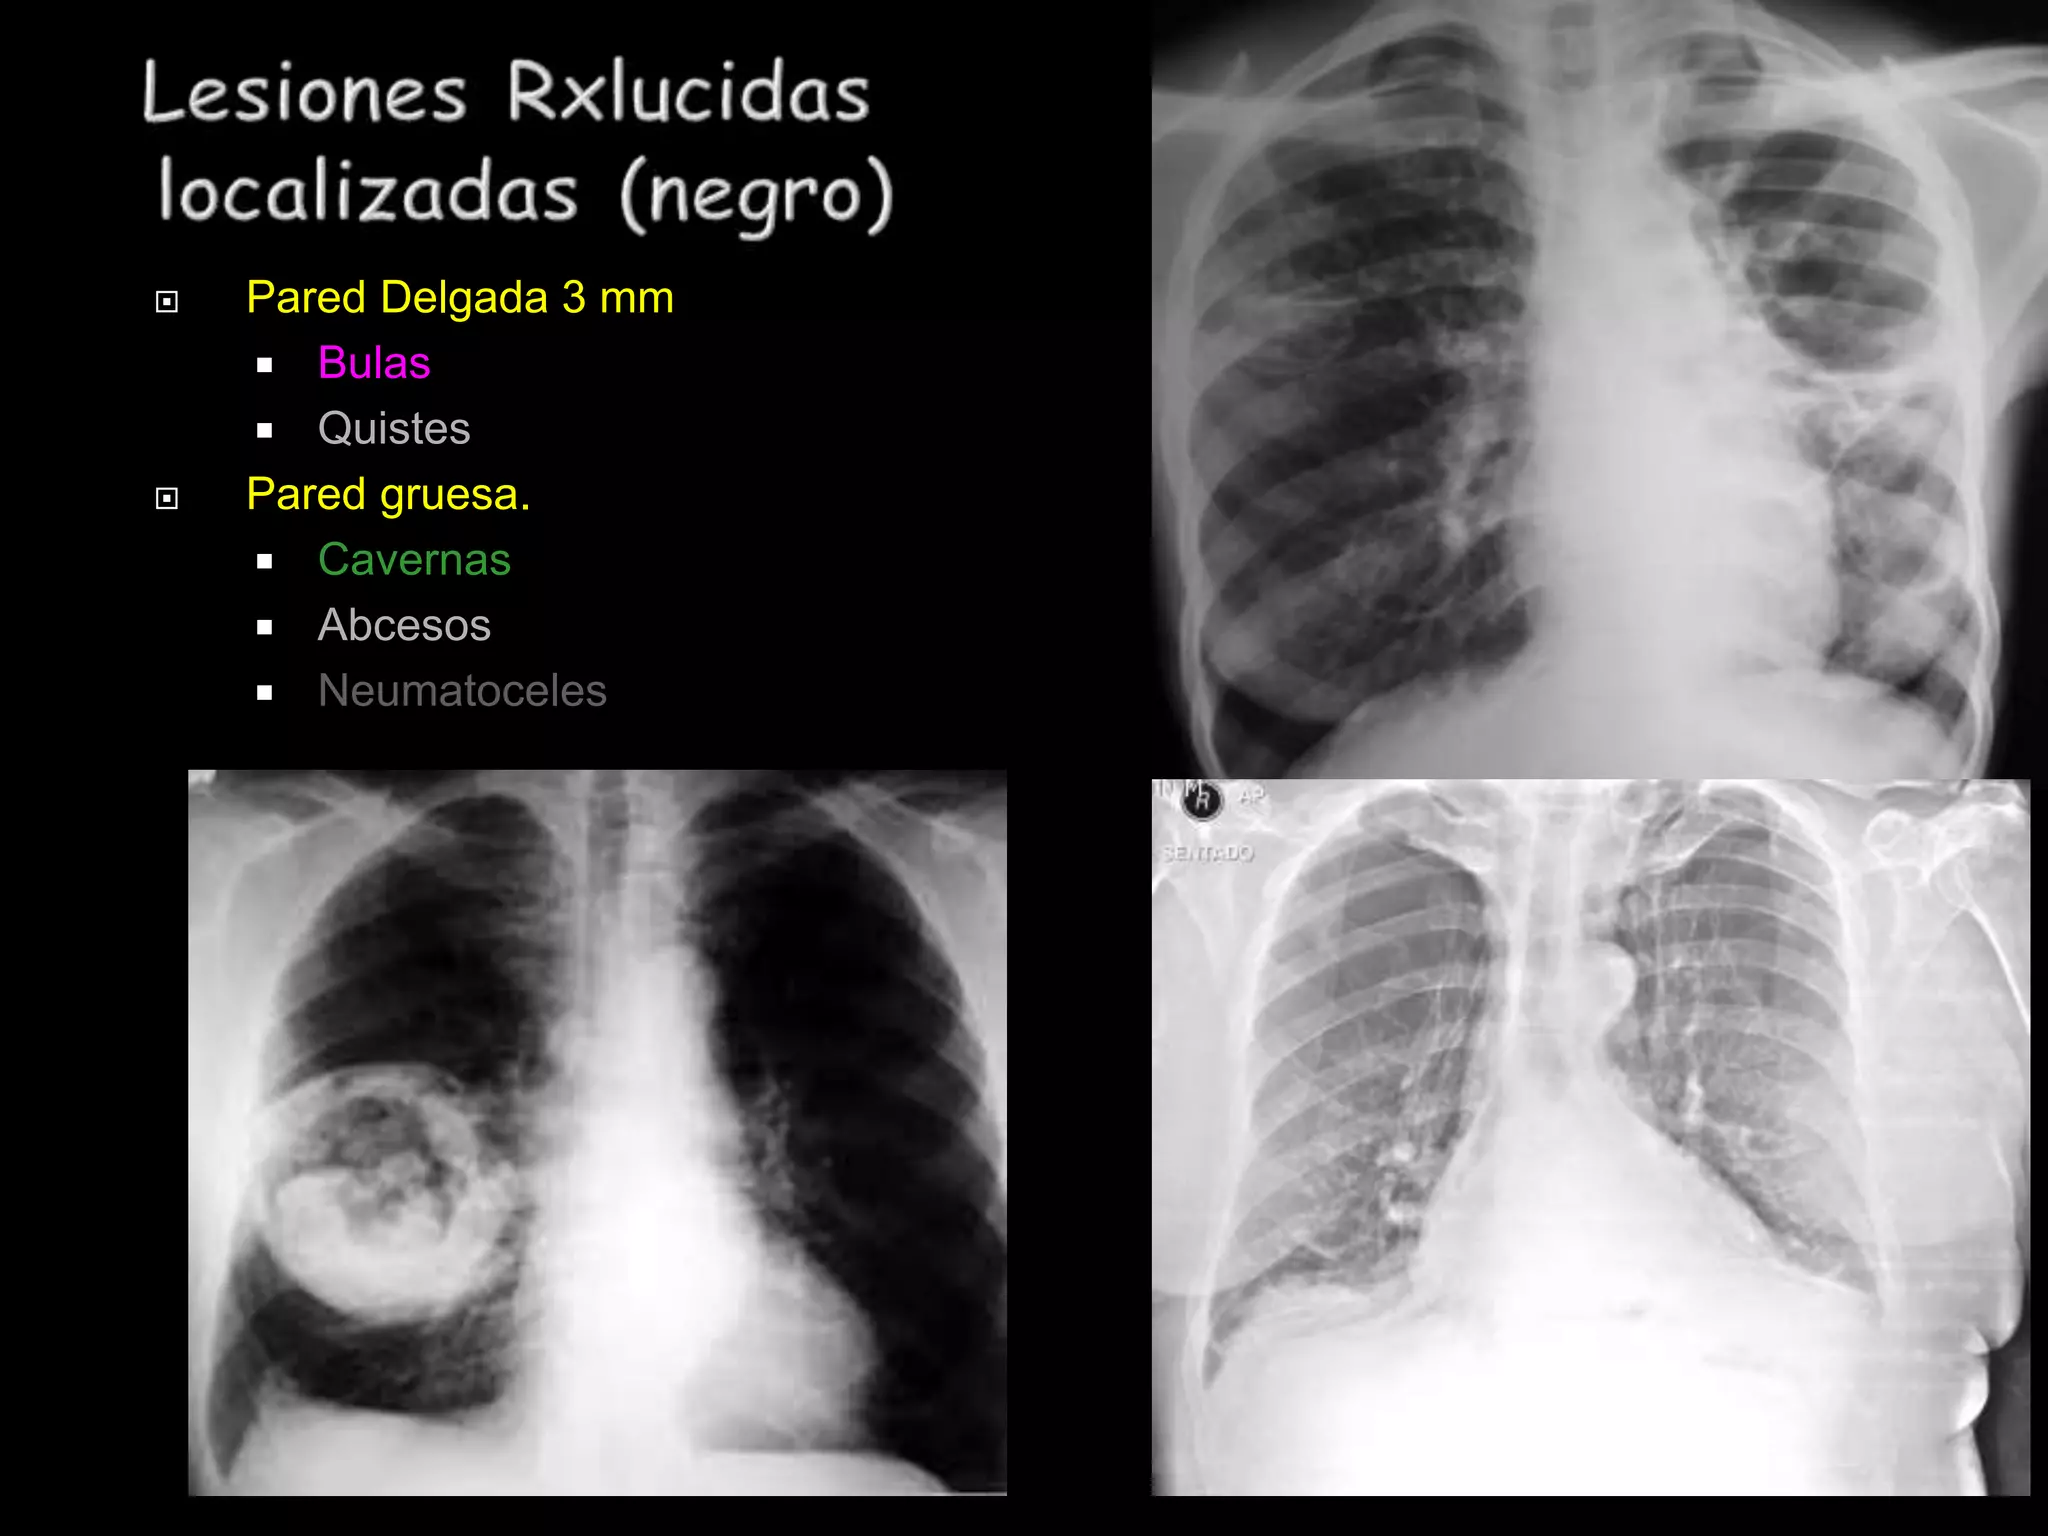

Este documento proporciona una lista de términos radiológicos relacionados con el tórax y los pulmones. Incluye descripciones breves de diferentes patrones de opacidad pulmonar como consolidación, neumotorax, nódulos y cavernas, así como sus posibles causas. También cubre términos relacionados con el mediastino y las técnicas de imagen torácica.